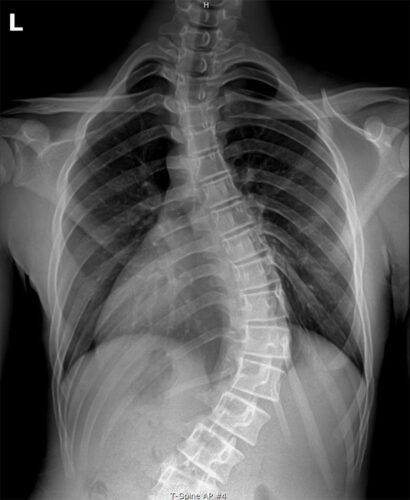

- الفحص السريري

- تقييم حركة الجسم

- الأشعة